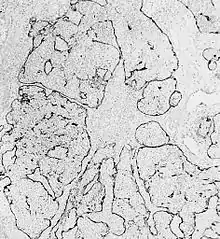

Esthesioneuroblastoma is of neurocrest origin, arising from olfactory sensory cells in the olfactory epithelium.[1] The olfactory epithelium consists of olfactory sensory cells, sustentacular cells and basal cells.[1] Esthesioneuroblastoma consists of lobular sheets with neurofibrullar fibers and rosettes.[4] Hyam's classifications are an important way of determining prognosis.[10]